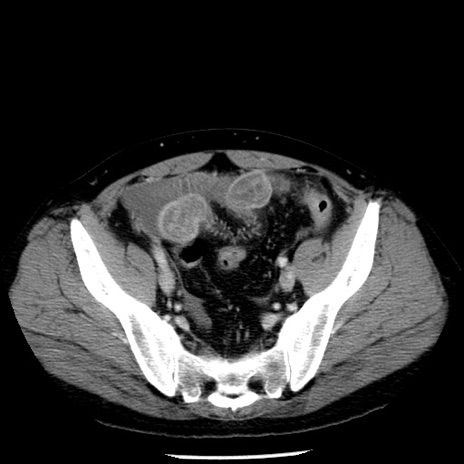

症例29(横断像)

【症例】40歳代男性

【現病歴】2日前から胃痛あり。徐々に周期的な激痛に変化した。本日になっても激痛があるため受診。

【身体所見】意識清明、BT 38-39℃台あり、腹部:膨満、やや硬、右下腹部に圧痛あり。

【データ】WBC 8500、CRP 23.26